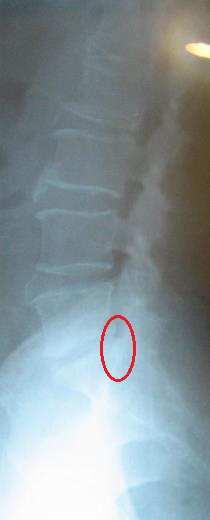

척추관 협착증

척추관 협착증은 선천적으로 척추관이 정상보다 좁게 태어난 사람이 젊을 때는 이상이 없다가 나이가 35세 혹은 40세 이상이 되어, 뼈와 인대의 변성이 겹쳐서 일어나는 수가 있는데 35세 전에는 비교적 드뭅니다.

척추관 협착증은 협착의 정도에 따라 치료 경과가 다른데 치료 반응이 떨어지는 형태의 협착증이 있으나 바태추나적 관점에서 검진한 후 바태추나가 타당하다고 여겨지는 경우 3개월 정도의 치료 후 호전 될 수 있다.